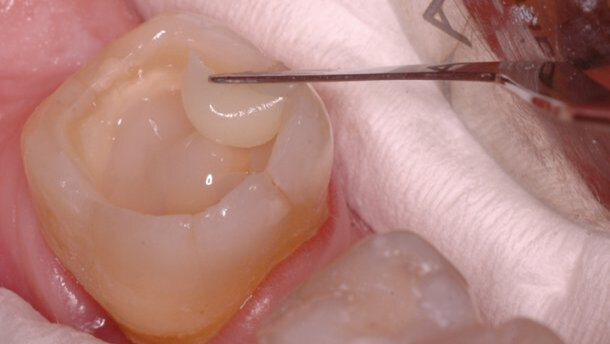

Planiranje restauracije zuba je predstavljalo problem. Iako je zub imao očuvana četiri zida krunice (sl.2), pretpostavljeno je da bi se oni posle brušenja veoma istanjili ili potpuno nestali tako da smo se odlučili na primenu retencije unutar kanala korena. Međutim, prilikom uklanjanja prethodnog definitivnog punjenja kanala je utvrđeno da je ono u sebi sadržalo eugenol. Po mišljenju mnogih autora eugenolom kontaminirani kanal korena predstavlja kontraindikaciju za adhezivno cementiranje kočića ojačanih vlaknima. Iz tog razloga smo se odlučili za primenu metalnih kočića malog dijametra (NORDIN©, GOLD PLATED COMPOSITE SCREW POST), ali postavljenih u sva tri kanala. Na taj način smo maksimalno štedeli tkivo zuba i postigli dovoljnu retenciju kompozitnog materijala. Kočići su cementirani glas jonomer cementom (GC Fuji PLUS) koji je istovremeno predstavljao barijeru za prodor eventualno zaostalog eugenola iz kanala korena (sl.3). Tako su stvoreni preduslovi za uspešnu primenu dentin vezujućeg sredstva u kruničnom delu. Primenjeno je dvokomponentno samonagrizajuće dvostruko polimerizujuće dentin vezujuće sredstvo (GRADIA© CORE SELF-ETCHING BOND)(sl.4). Kod ovog sredstva nije potrebno nagrizanje i ispiranje tako da smo izbegli kvašenje glas jonomer cementa kojim su cementirani kočići. Želeli smo da budemo sigurni da je polimerizacija uspešno sprovedena i u dubokim delovima kaviteta, a i u onima koji su prilikom osvetljavanja led lampom ostali u senci metalnih kočića. Kao materijali za restauraciju su korišteni GRADIA© CORE ojačani kompozitni materijal za nadogradnje i G-enijal© Posterior (GC). Gradia CORE materijal je upotrebljen za popunjavanje kaviteta do nivoa na kome će se nalaziti okluzalna površina budućeg obrušenog patrljka(Slike 5 i 6). To je uradjeno zato što je to materijal koji je po svojim fizičko-hemijskim karakteristikama projektovan da može da bude zamenik za tkivo zuba na kome je planirana izrada krunice ili mosta. Drugi razlog je što je to materijal koji je dvostruko polimerizujući pa će sigurno biti polimerizovan i u delovima kaviteta do kojih svetlo polimerizacione lampe nedovoljno dopire. Treći razlog je što je njegova aplikacija iz kertridža sa mikrokanilom pogodna za primenu u kavitetu sa kočićima gde je teško postaviti materijale iz tube koji se štopuju nabijačima. Vrlo je važno da u restauraciji ne budu mesta koja su ispunjena vazduhom.

Preostali deo kaviteta je restauriran svetlosno polimerizujućim materijalom iz tube (G-aenial© Posterior) zato što je to materijal po svojim fizičko hemijskim karakteristikama predviđen za definitivne restauracije u bočnoj regiji (slike 7,8 i 9). Površina materijala je otpornija na sile koje nastaju prilikom mastikacije u odnosu na Core materijal, a njegova završna obrada dovodi do boljih funkcionalnih i estetskih rezultata (sl.10). Taj deo ispuna će biti uklonjen prilikom brušenja zuba za most, ali je ta procedura morala da bude odložena na duže vreme.